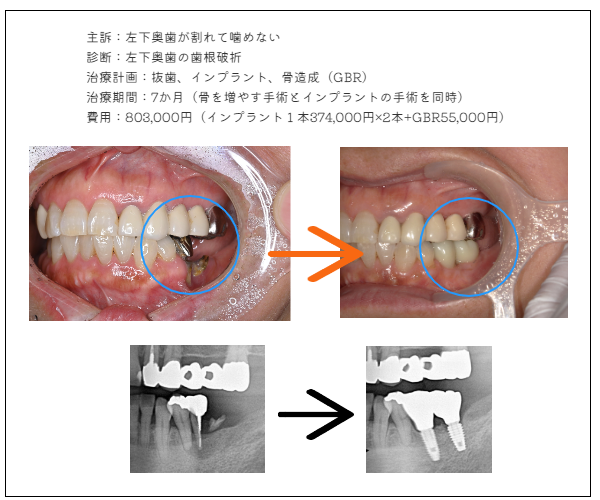

imprant症例2

MYデンタルインプラント